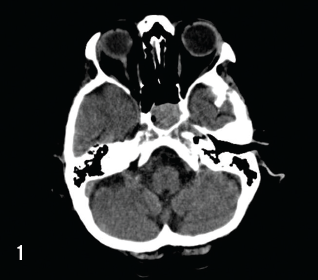

Multiple Myeloma

Armin Jegalian, MD, PhD; Ronan Factora, MD

A 71-year-old female with a past medical history of hypertension presented to the emergency department with an 8-week history of neurological symptoms including confusion, short-term memory loss, and...